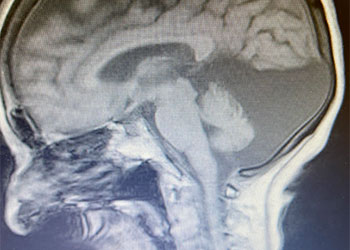

Hydrocephalus and Brainstem Tumor

Cerebellar Hemangioblastoma